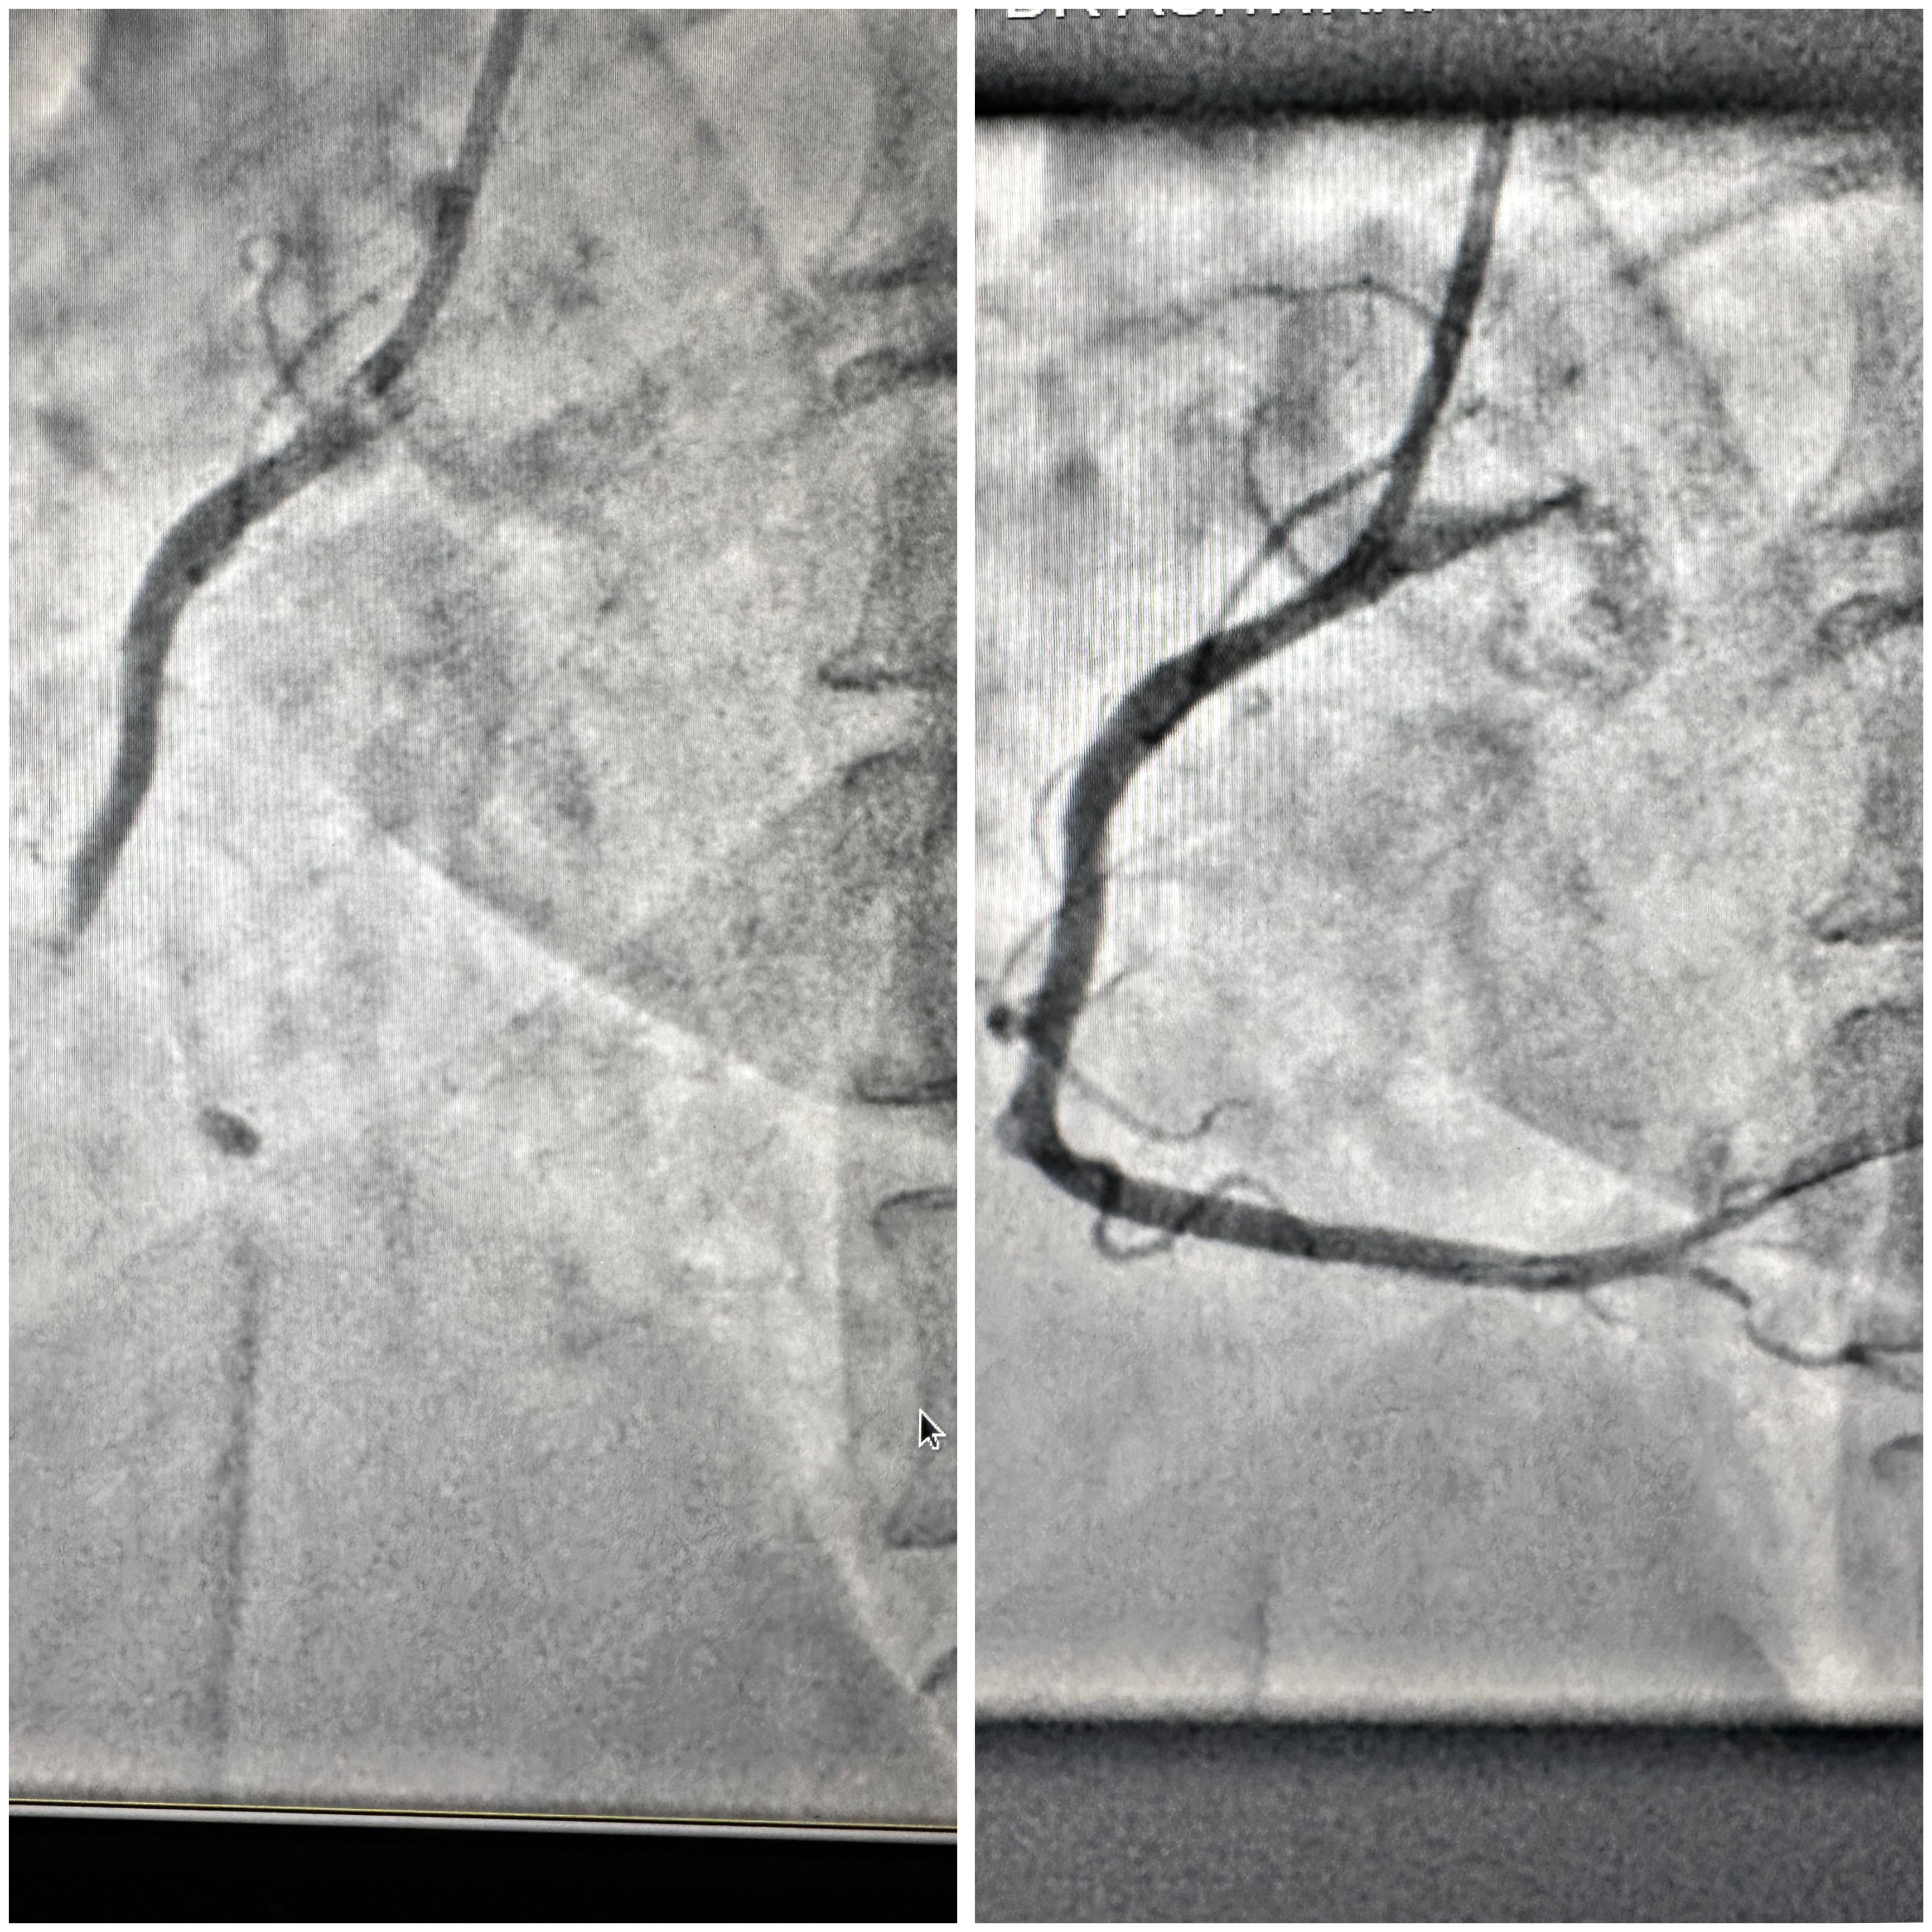

Angioplasty/Stenting

Angioplasty, also called Percutaneous Coronary Intervention (PCI), is a medical procedure used to open narrowed or blocked arteries in the heart. It restores blood flow and helps prevent heart attacks or other cardiac emergencies.

A thin tube called a catheter is inserted through an artery—usually in the groin, wrist, or arm. At the tip of the catheter, there's a small balloon. Once it reaches the blocked artery, the balloon inflates. This pushes plaque against the artery walls, widening the passage.